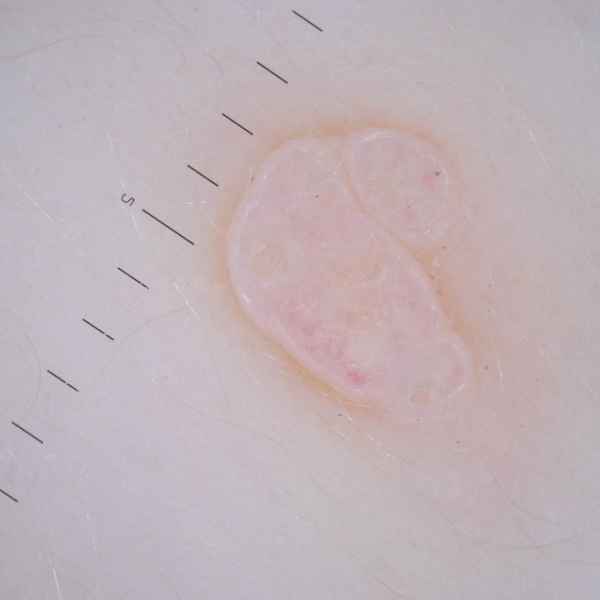

Моллюск контагиозный